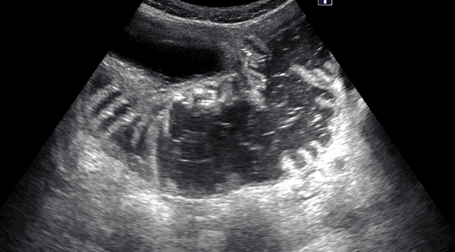

診断・検査方法

• 超音波検査